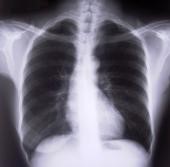

Tüdőszűrés

A 2022. évi tüdőszűrésre május 11. (szerda) és május 30. (hétfő) között kerül sor Biatorbágyon. A tüdőszűrés helye:a Juhász Ferenc Művelődési Központ kiállítóterme (2051 Biatorbágy, Baross Gábor u. 4.) A vizsgálat ideje: hétfőtől péntekig 8:00-17:50 óra között.

A tüdőszűrés a felnőtt lakosság számára ajánlott vizsgálat! Panasz nélkül is lehet beteg. A vizsgálat alkalmas a TBC, illetve sok más tüdőbetegség időben történő felismerésére. A szűrővizsgálat 40 év feletti lakosoknak évente egy alkalommal továbbra is ingyenes. 40 éves kor alatt, illetve munkahelyi alkalmassági vizsgálathoz a vizsgálat díja 1700,- Ft, mely az OEP által országosan elrendelt összeg. Ebben az esetben postázzuk az eredményt egy felbélyegzett válaszboríték ellenében. A befizetés a szűrőállomáson kapható csekken történik. A 14-18 év közötti személyek szűrése ingyenes, de beutaló és szülői beleegyező nyilatkozat szükséges. A törvény által kötelezetteknek a vizsgálat természetesen ingyenes.